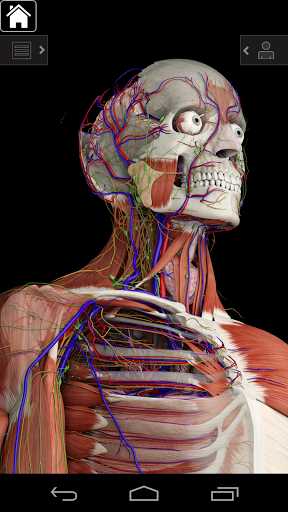

Essential Anatomy 3 reprezentuje najnowsze przełomowe technologie 3D i innowacyjny design. Najnowocześniejszy silnik graficzny 3D, zbudowany na zamówienie przez 3D4Medical od podstaw, zapewnia bardzo dokładny model anatomiczny i zapewnia doskonałą jakość grafiki, której żaden inny konkurent nie jest w stanie osiągnąć.

Aplikacja przedstawia unikalne podejście do uczenia się ogólnej anatomii. Grafika jest nieporównywalna i sprawia, że uczenie się, dzięki wykorzystaniu treści informacyjnej i innowacyjnych funkcji, jest bogatym i wciągającym doświadczeniem.

Essential Anatomy 3 jest responsywny, wizualnie oszałamiający i pozbawiony wysiłku. Aplikacja jest w pełni 3D, co oznacza, że możesz zobaczyć dowolną strukturę anatomiczną w izolacji, a także pod dowolnym kątem.

---- Ponad 4000 bardzo szczegółowych struktur anatomicznych